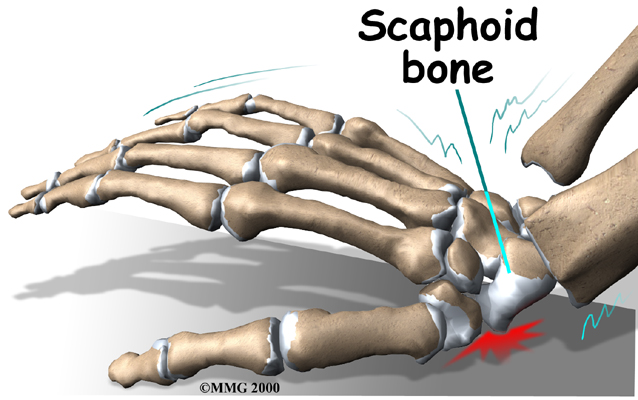

A fall on the outstretched hand puts heavy stress on the scaphoid bone. This stress can cause either a small crack through the middle of the bone or a complete separation of the bone into two pieces. A separation is called a displaced fracture.

A scaphoid fracture is almost always caused by a fall on the outstretched hand. We commonly try to break a fall by putting our hands out for protection. Landing on an outstretched hand makes hand and wrist injuries, including a fracture of the scaphoid bone, fairly common.

When a scaphoid fracture is recognized on the first X-ray, treatment begins immediately. But patients often assume that the injury is just a sprain, and they wait for it to heal on its own. In some cases, the wrist gets better. In many cases the bone fails to heal. The scaphoid fracture then develops into what surgeons call a nonunion.